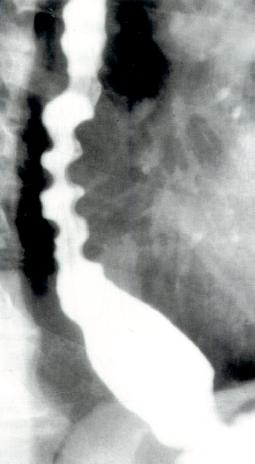

食管X线吞钡检查

DES患者可见非蠕动性同步收缩形成的节段性钡柱,称为“开塞钻食管”(图2.9)。钡透视亦可用于除外其他疾病的可能性。

DES病人X线吞钡检查显示开塞钻食管

图2.9DES病人X线吞钡检查显示开塞钻食管。